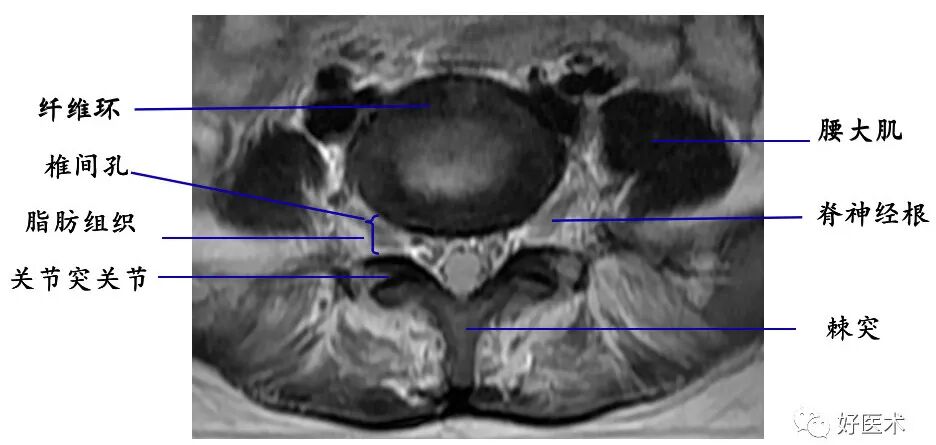

4. 椎管及内容物

硬膜外脂肪:低密度影

硬脊膜囊:呈圆形或椭圆形软组织密度影。CT平扫不能区别硬脊膜囊、脑脊液和脊髓。

椎内静脉丛:位于硬膜外间隙内,在CT平扫上不能单独显示,增强扫描呈点状高密度影。

脊髓:位于椎管中心呈中等信号影

脊神经根:中等信号条状或圆点状影。

硬膜外脂肪组织:

T1WI上呈连续条状或带状高信号;

T2WI上呈中高信号。

椎内静脉丛:呈网状略低信号影。

椎间孔:位于椎管前外侧,其内的脊神经根呈软组织密度,周围有低密度的脂肪组织环绕

充填椎间孔的脂肪组织呈高信号;

行走于其中的脊神经根呈圆形、长圆形低或等信号影

椎间盘:呈软组织密度影,CT值为70±5HU,不能区分髓核和纤维环

髓核:T2WI上呈较高信号

纤维环:T1WI和T2WI上均显示为低信号

sharpey纤维:T1WI和T2WI上均显示为低信号

透明软骨板:T1WI和T2WI上均显示为低信号